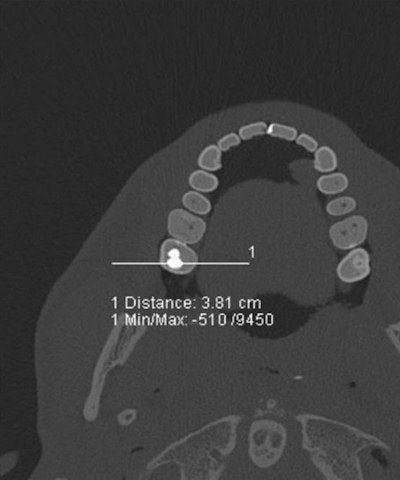

A case in point is the visualization of dental fillings. Dental x-ray plays a key role alongside DNA in identifying human remains whether in mass fatalities or single incidents when bodies have undergone alteration after death. Up to 80% of postmortem identification in the wake of the Asian tsunami in 2004 was based on dental status. Ultrahigh-resolution dual-source CT with extended CT scale has proved to reduce streak-induced artifacts and distinguish between fillings, whether composite, amalgam, ceramic, or temporary fillings, based on radiopacity in Hounsfield units, their size, and location.

Cross section of investigated teeth and Hounsfield unit profile along a measurement indicated as a white line in the molar. All images courtesy of Dr. Christian Jackowski.